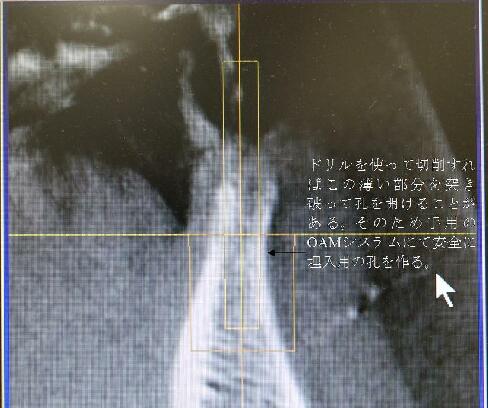

いるところです。3ミリのインプラント体を埋入するには骨が薄すぎます。ドリルでの切削では外側の壁に穴が開いたりドリルが突き抜けたりします。大変危険ですが多くの大学病院や歯科医院ではドリリングで対応してるのが現状です。

横から見た写真です。

このように2ミリ間隔の器具にて徐々に骨を広げるため骨の外側の壁を突き破ることなく安全にインプラントの埋入孔を開けることが出来ます。